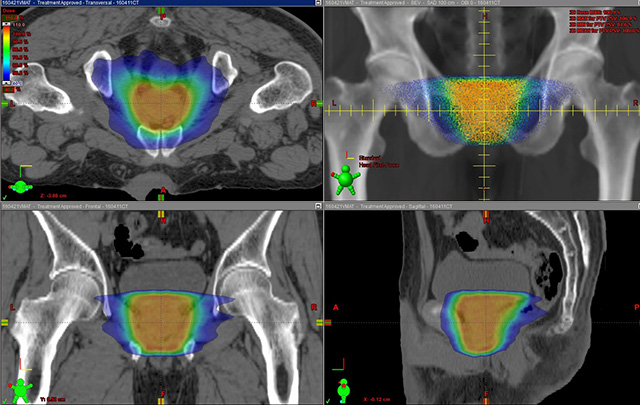

IMRT[強度変調放射線治療]

病巣へ放射線を集中させ、病巣の周りにある正常な組織への放射線の影響を最低限に抑え、治療を行います。

体外照射は複数のリニアックを使った最適なエネルギーのX線や電子線を使用し、副作用の少ない治療を行っています。コンピュータ制御で、がん病巣だけに集中照射しながら、周囲の正常組織にほとんど照射されない定位放射線治療(SRT2022年治療人数:脳44人、肺37人、その他20人)や強度変調放射線治療(IMRT2022年治療人数:頭頸部43人、前立腺76人、中枢神経21人、その他89人)を症例に応じて実施しています。IMRTの進化形で、より短時間の治療が可能な強度変調回転照射(VMAT)、さらに呼吸同期放射線治療や画像誘導放射線治療(IGRT)の組み合わせにより高精度の治療が可能であり、適応症例も順次拡大しています。また、症例に応じてRALSによる高線量率(HDR)やCs-137などによる低線量率(LDR)の小線源治療も行っています。形態や機能を温存し、生活の質(QOL)を維持できる放射線治療は、根治的治療はもちろん進行がんや再発・転移がんに対しても有効です。